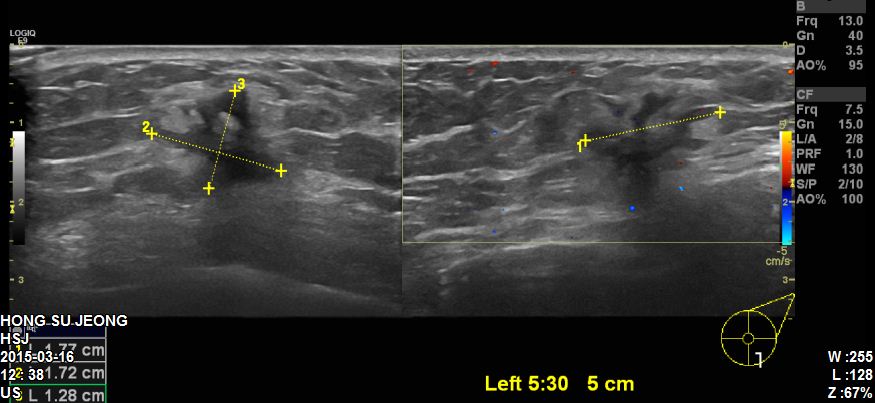

본원에 내원하신 60대 환자분이십니다.

타원에서 진행한 초음파 확인 후 좌측유방 5 : 30 방향에 있는 1.7cm의혹

조직검사 시행하였고 결과상 침윤성유관암 진단되었습니다.